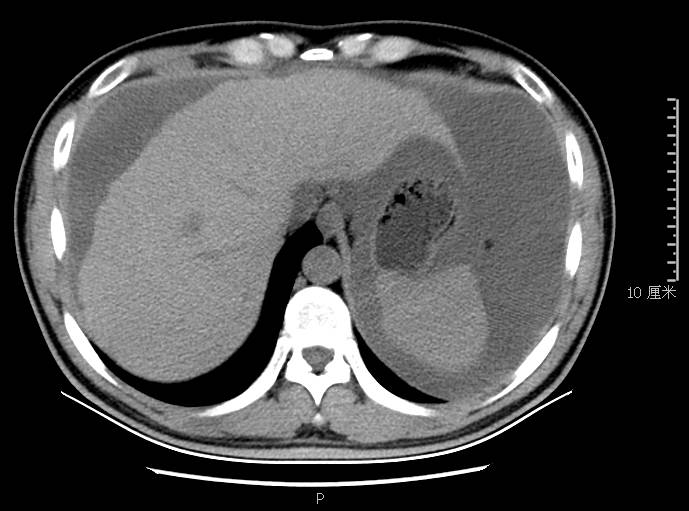

全腹CT:(1)结合病史考虑腹膜炎(见图2A),大量腹水;(2)右骼窝区管状样结构,考虑阑尾扩张(见图2B);(3)肝脏多发小囊肿(见图2C);(4)肝内胆管轻度扩张,建议隔期复查。

本例确诊后对B超及CT再次回顾发现:腹腔、盆腔可见不均质中强回声包块,部分呈囊实状,腹膜增厚,大网膜成饼状(如图2A)和肝周可见不均质中强回声弧形压迹、脾周可见不均质中强回声包饶,肝脏成扇贝样改变(如图2C),但在诊断报告中未提及。有学者发现mantle和scalloping(如图2A,2C)在PMP中具有代表性,且mantle较scalloping更为常见,若mantel征同时伴有大小不一的囊性改变,则更具诊断价值。

图2c肝脏成扇贝样改变(肝脏由于受肿瘤实质性或囊性组织压迫而其实质却未受侵犯,于是在一处或多处呈下凹状或扇形皱褶状(scalloping)

通过本病例分析认为此类患者,腹穿时若发现腹水不易抽出或抽出物为黏稠胶冻样,腹部B超提示液性暗区内有漂浮的团状回声有分隔,撞击腹部后可出现“礼花”样改变,肝脾包膜完整不光滑,有弧形压迹,全腹部CT示弥散占位,可见mantle和scallping征、大网膜成饼状且阑尾扩张应高度怀疑本病。